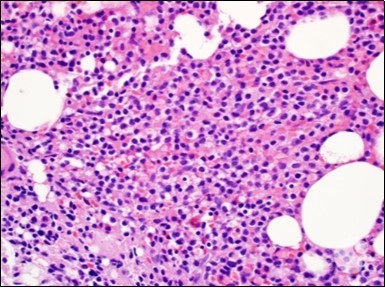

Figure 1.HCL: hairy cells infiltrating designated spaces(17).

HCL: hairy cells infiltrating             designated spaces(17).